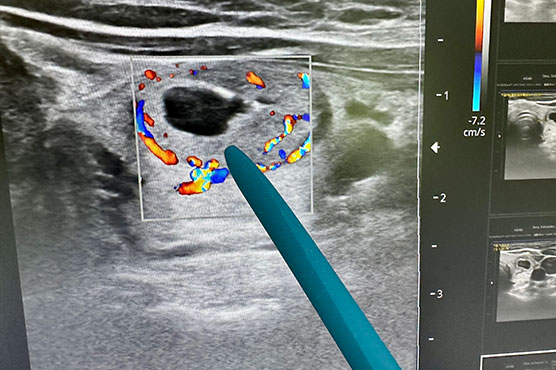

Elevate your bedside assessment skills with this immersive two-day Neonatal and Pediatric POCUS course, designed to take you from essential ultrasound fundamentals to advanced, physiology-based hemodynamic decision-making. Through a dynamic blend of concise expert-led talks, high-yield case discussions, and extensive hands-on scanning in small groups, participants will build confidence in lung, cardiac, vascular, and abdominal ultrasound applications. Whether you are new to POCUS or looking to expand into targeted functional echocardiography, this course delivers practical tools you can apply immediately to improve care for critically ill infants and children.